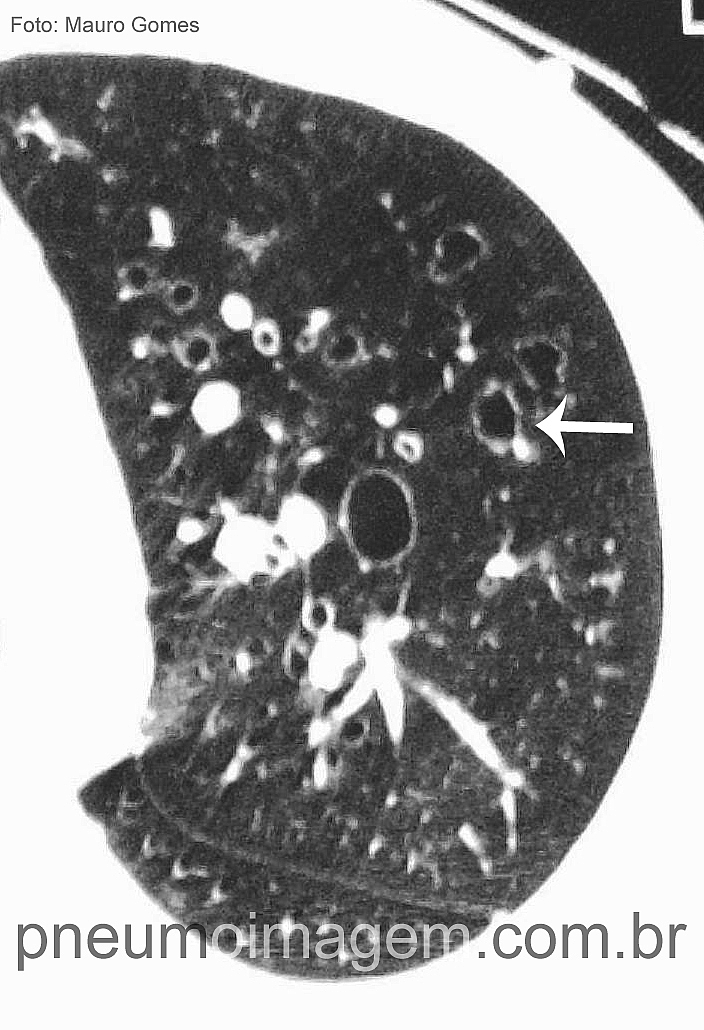

CAIXA DE FERRAMENTAS PARA BRONQUIECTASIAS: ACESSE GRATUITAMENTECom base em diretrizes nacionais e internacionais, a Caixa de Ferramentas para Bronquiectasias (Bronchiectasis Toolbox) foi desenvolvida por um grupo de membros da Thoracic Society of Australia and New Zealand (TSANZ), todos com ampla experiência no manejo de pessoas com bronquiectasias. Em seis subcategorias, a Caixa de Ferramentas é facilmente navegada para encontrar informações atualizadas e baseadas em evidências sobre vários tópicos, incluindo diagnóstico, avaliação/revisão, gestão médica, estratégias de fisioterapia, farmacologia, função pulmonar e doenças associadas.